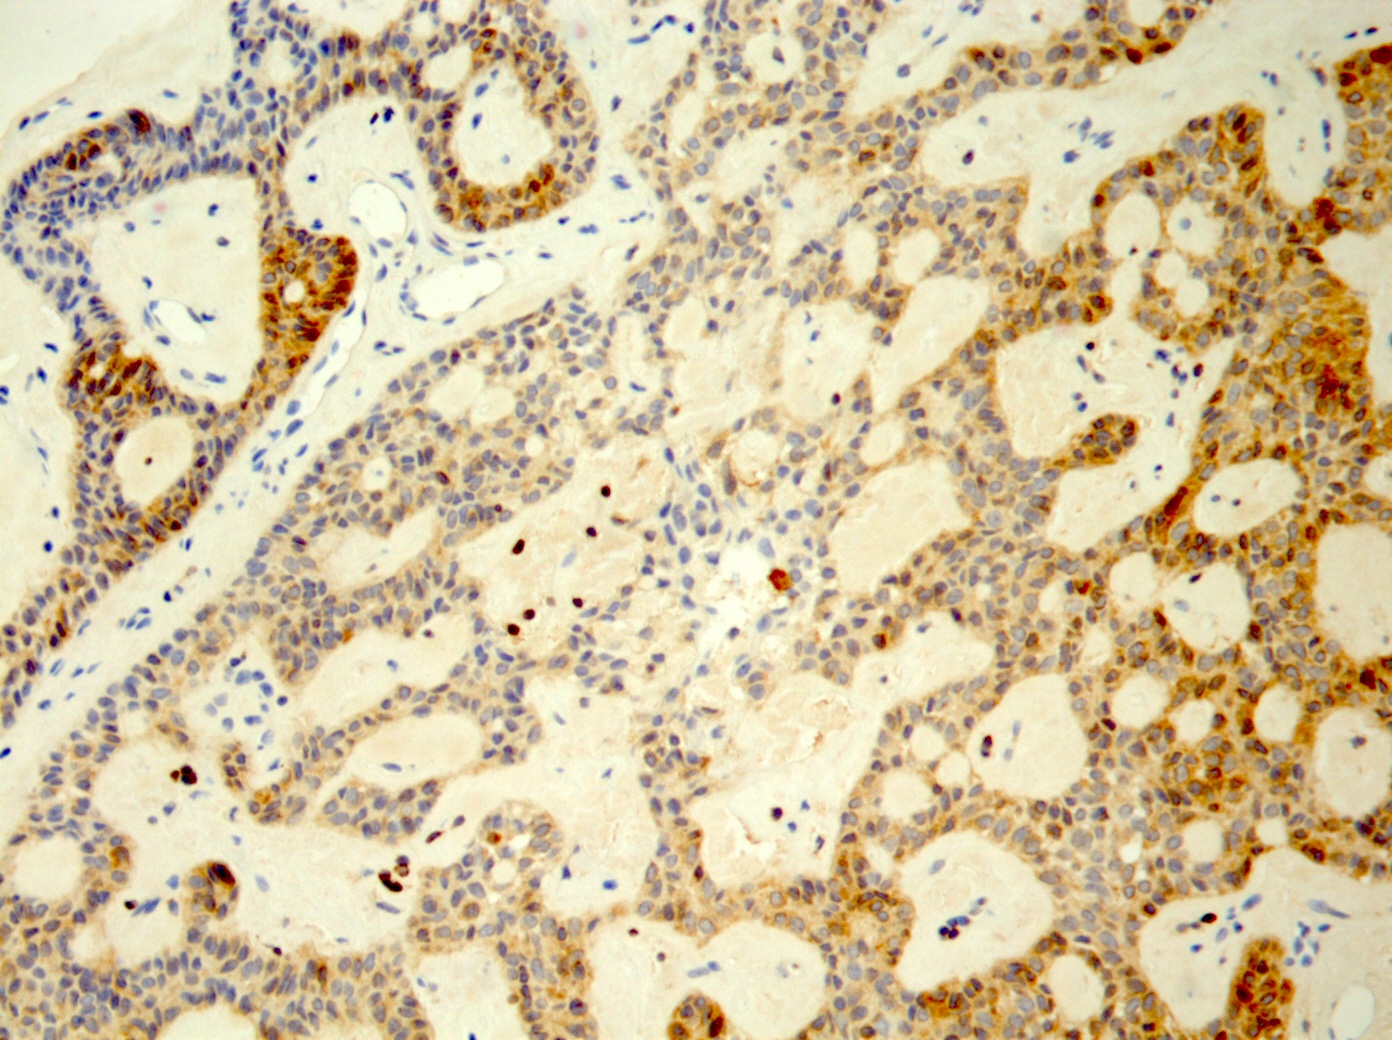

Positive stains

- S100, AE1 / AE3, CK19

- Pancytokeratin (heterogeneous intensity), CK7, CK8, CK13, CK14 basally (Gerodontology 2014;31:320)

- Focal GFAP; distinctive linear immunoreactive pattern of GFAP among cells in proximity to connective tissue interface (Gerodontology 2014;31:320)

- CD117 (Pol J Pathol 2013;64:71)

- BCL2

- Varied p63 expression, nuclear p63 in squamoid foci, lack of p63+ duct surrounding cells (Appl Immunohistochem Mol Morphol 2016;24:501, J Craniomaxillofac Surg 2017;45:1754, Adv Ther 2019;36:1950, Am J Surg Pathol 2022;46:190)

- Nuclear CAM 5.2, nuclear SOX10, nuclear and cytoplasmic p16, vimentin variably positive (J Craniomaxillofac Surg 2017;45:1754)

- Squamous balls: p16 and CK5/6 positive

- Heterogeneous, moderate to strong cytoplasmic WT1 (periphery of ribbon-like structures); in microadenomatous foci, associated with cuboidal cells (Pathol Res Pract 2014;210:726)

- Stroma: blue on Alcian blue / PAS stain and CD15+ (Adv Ther 2019;36:1950)

Microscopic (histologic) images